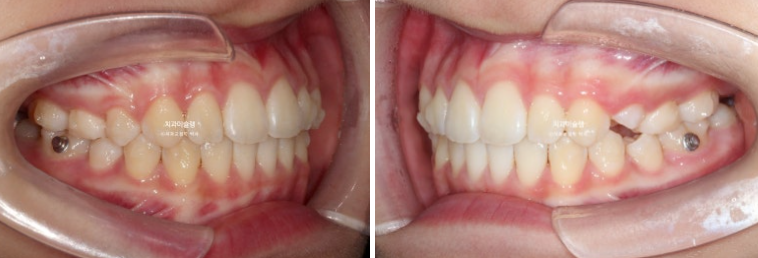

24.04

앞니가 유독 사이즈도 크고 아래로 내려와 있습니다.

측면에서 보면 뻗쳐서 튀어나와있죠

유치가 위 아래 합쳐서 아직 5개가 남아있어 인비절라인 퍼스트 어린이 교정 권유드렸습니다.